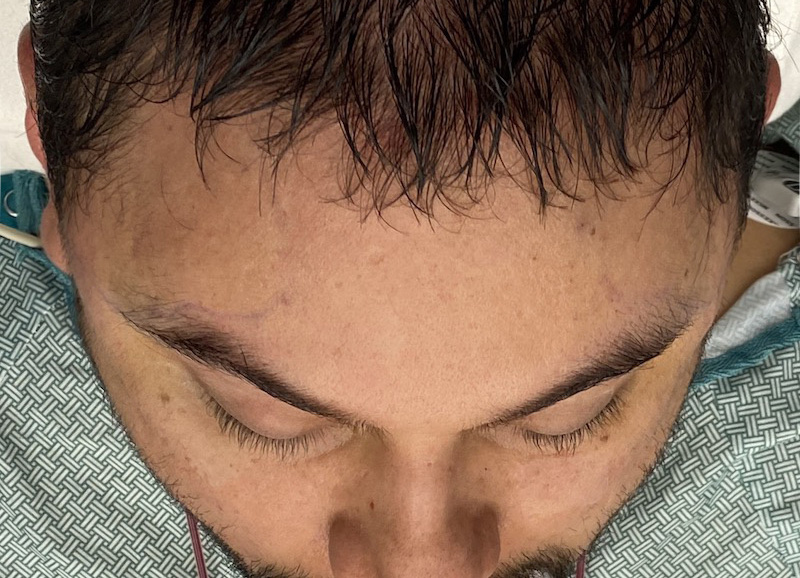

Desire for head shape asymmetry improvement as the final stage of total skull reshaping surgeries. (previous skull implants are in green color)

Placement of custom temporal implant through an incision behind the ear.

Desire for head shape asymmetry improvement as the final stage of total skull reshaping surgeries. (previous skull implants are in green color)

Placement of custom temporal implant through an incision behind the ear.